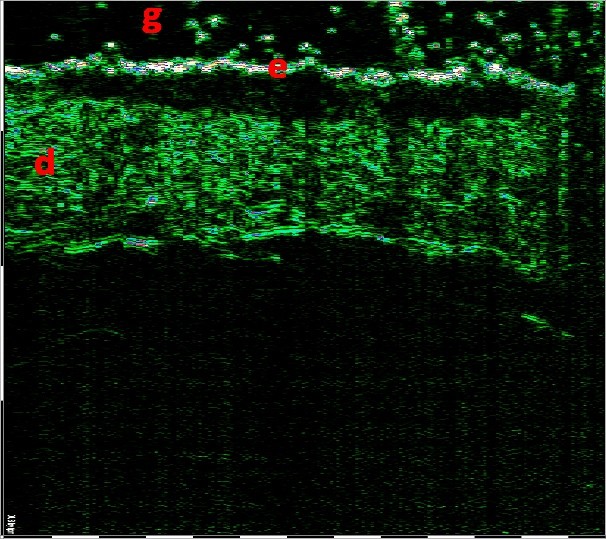

ΣΥΣΧΕΤΙΣΜΟΣ ΜΕΤΑΞΥ ΥΠΕΡΗΧΟΥ ΥΨΗΛΗΣ ΣΥΧΝΟΤΗΤΑΣ ΚΑΙ ΜΙΚΡΟΑΝΑΤΟΜΙΑΣ ΔΕΡΜΑΤΟΣ

Σάρωση άθικτου δέρματος στα 75 MHz (αριστερά) και διάγραμμα της μικροανατομικής δομής του δέρματος (δεξιά).

e – επιδερμίδα, pd – θηλώδες χόριο, rd – δικτυωτό χόριο, hf – θύλακας της τρίχας, bv – αιμοφόρο αγγείο βαθέος δερματικού πλέγματος, λίπος – λιπώδης ιστός, fas – περιτονία, msc – μυς.